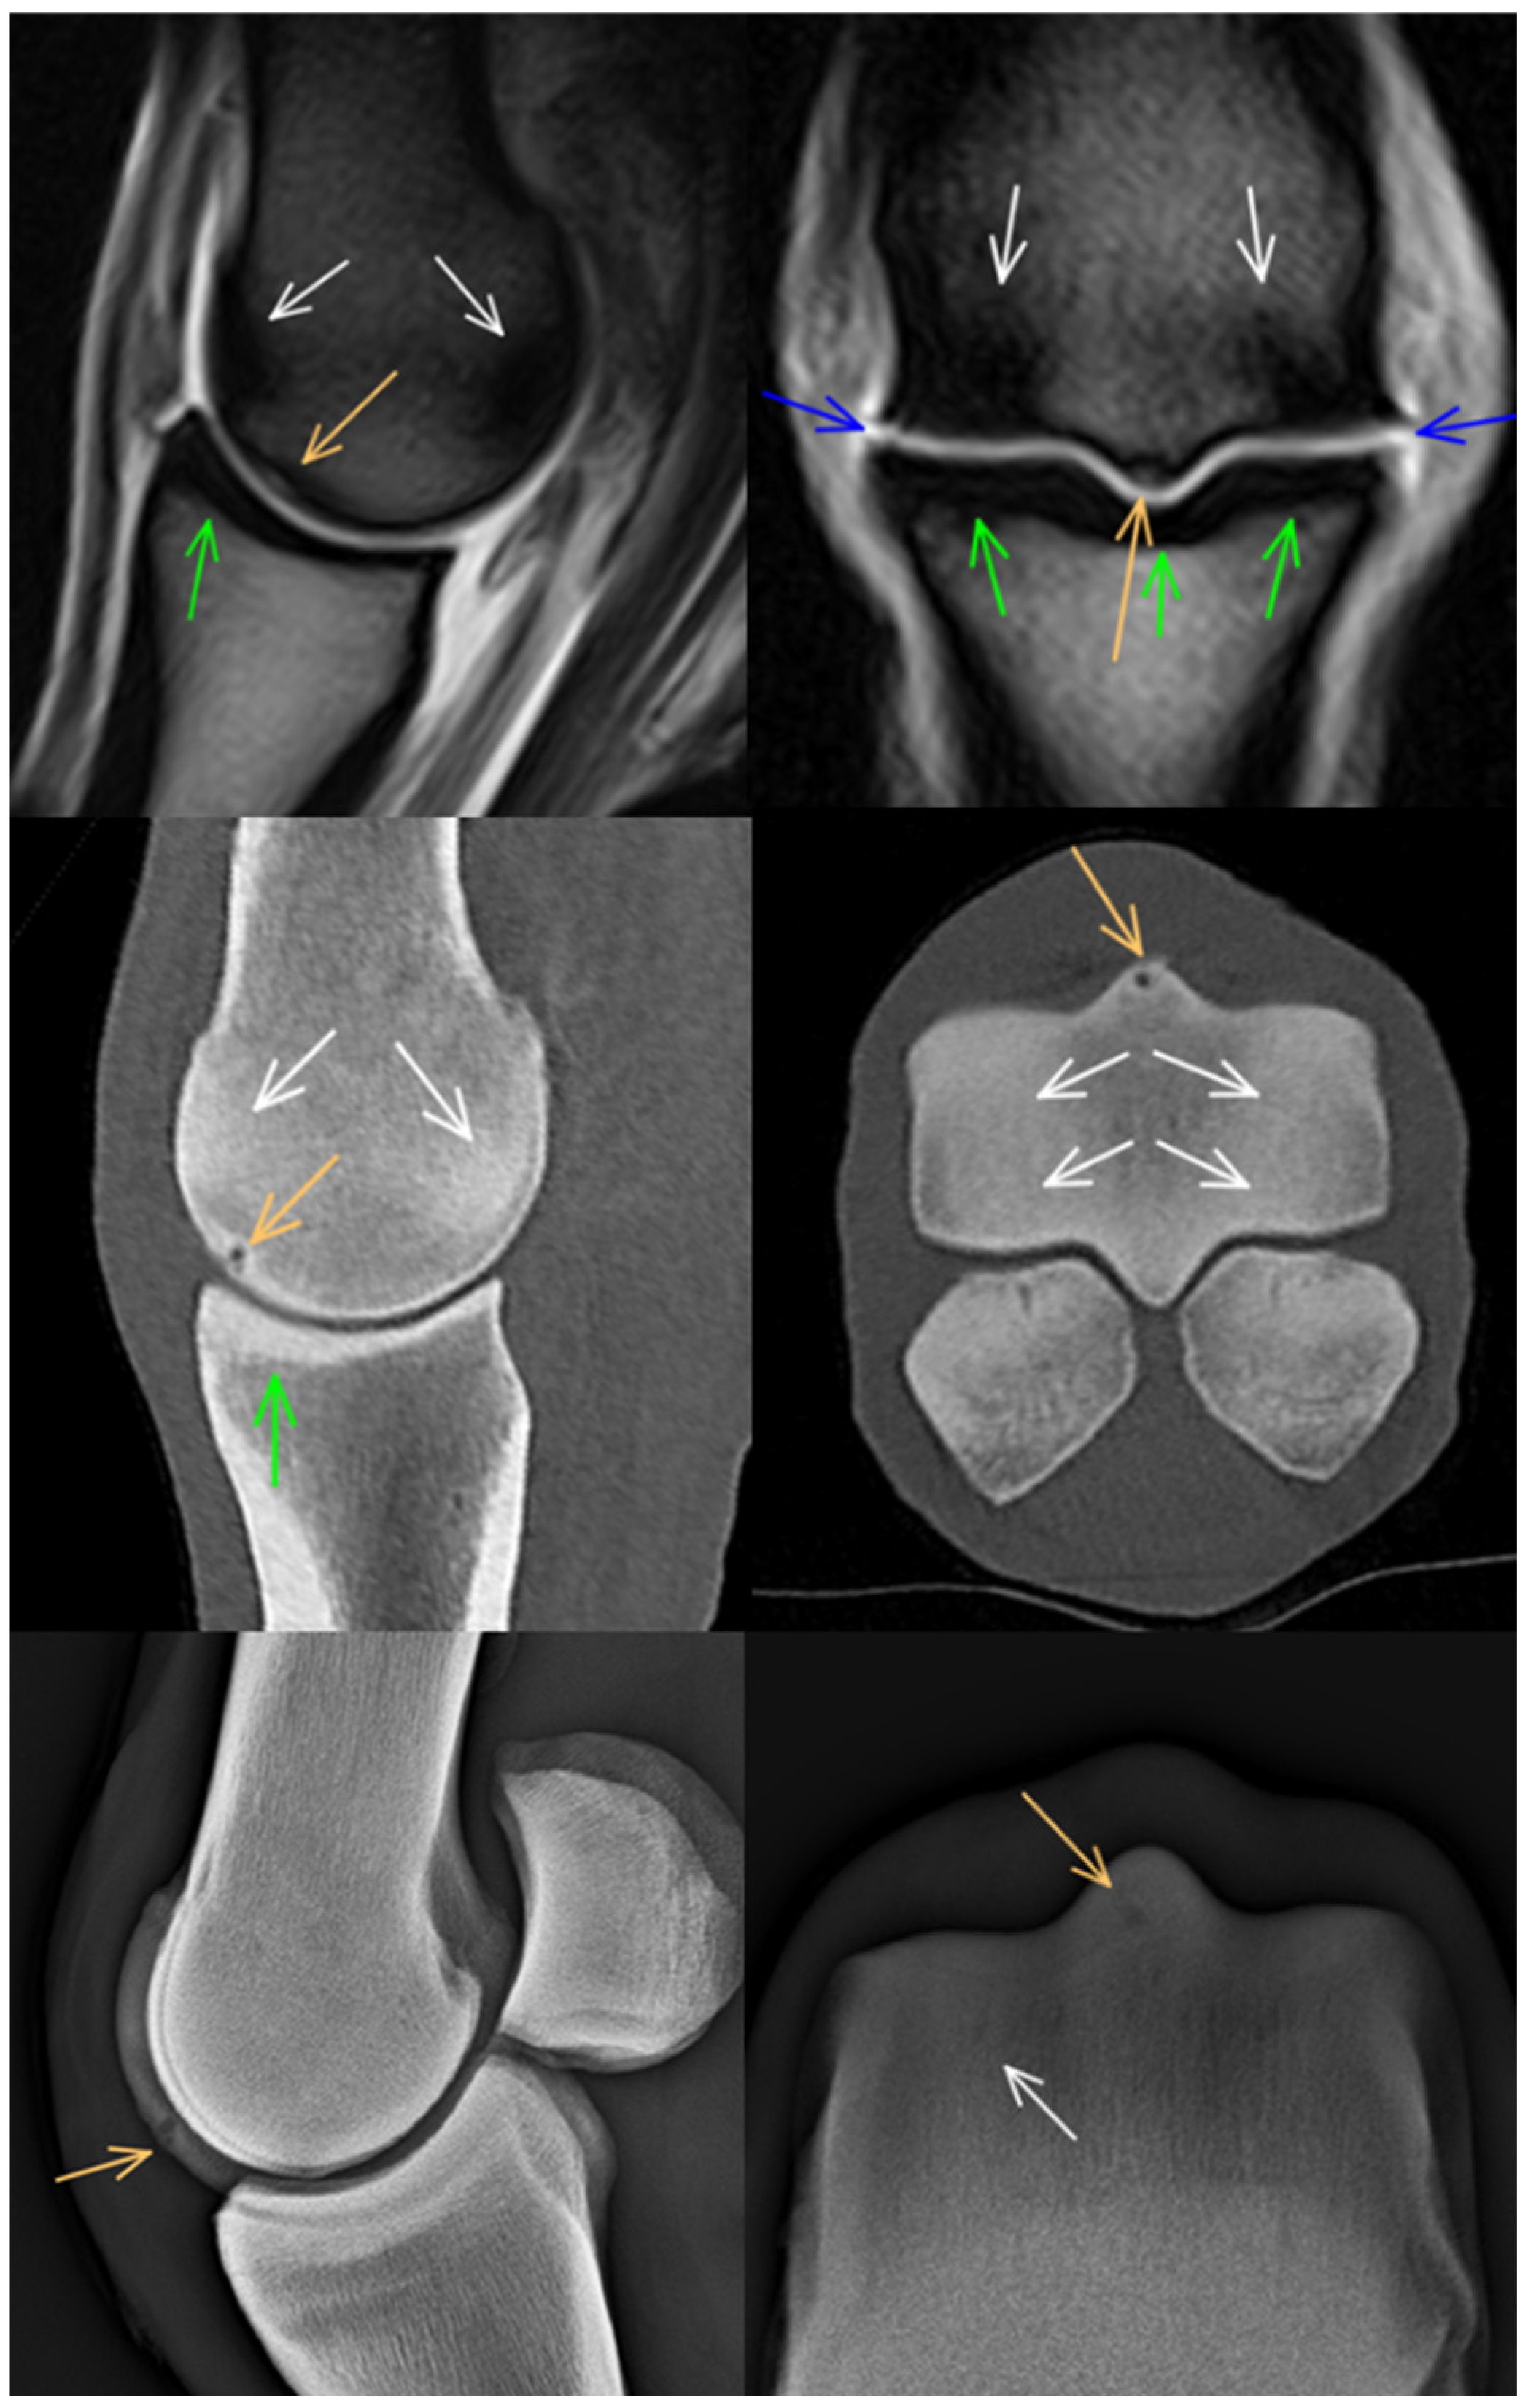

3.1. Third Metacarpal Bone

3.2. Proximal Phalanx

3.3. Proximal Sesamoid Bones

3.4. Soft Tissues